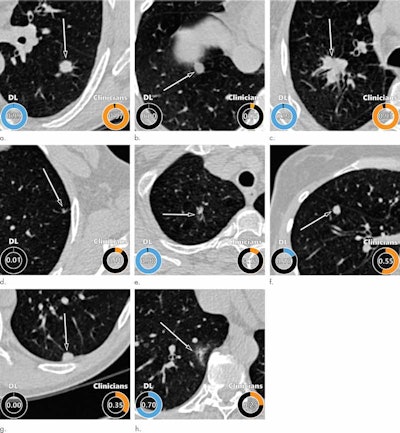

Examples of CT images in nodules from the Danish Lung Cancer Screening Trial (DLCST) with (a-d) high and (e-h) low agreement between the deep-learning algorithm and the clinicians for malignancy risk estimation. Numbers in rings on bottom left of each image are the algorithm's malignancy score, and numbers in rings on bottom right of each image are the clinicians' median malignancy score. The extent of the color filling is proportional to the malignancy risk (on a scale of 0 to 1, where 0 represents the lowest risk and 1 represents the highest risk). (a) Image shows a 15-mm spiculated and lobulated malignant nodule (arrow) classified correctly by the algorithm and clinicians. (b) Image shows an 11-mm smooth benign nodule (arrow) classified correctly by the algorithm and clinicians. (c) Image shows a 29-mm benign lesion (arrow) suspected to be a malignant nodule by both the algorithm and clinicians. This participant was diagnosed with pneumonia at clinical workup (Fig E4 [online]). (d) Image shows a 5-mm malignant nodule (arrow) called benign by both the algorithm and clinicians. The growth of the nodule can be seen from follow-up CT examinations (Fig E5 [online]). (e) Image shows a 15-mm part-solid malignant nodule (arrow) classified correctly by the algorithm and not suspected to be malignant by seven of 11 clinicians (Fig 6). (f) Image shows an 8-mm benign nodule (arrow) predicted to be moderately suspicious by the clinicians and called benign by the algorithm. (g) Image shows an 11-mm malignant nodule (arrow) predicted to be moderately suspicious by most clinicians but called benign by the algorithm. (h) Image shows a 16-mm benign lesion (arrow) classified correctly by the clinicians and predicted to be highly suspicious by the algorithm. Images and captions courtesy of the RSNA.